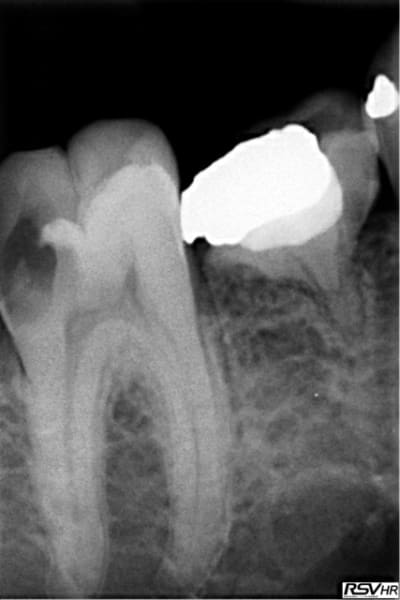

pour répondre à la question initiale du post, un cas de molaire dépulpée non couronnée.

Mise en place d'un cvimar (fuji II lc) en recouvrement de l'entrée canalaire puis onlay Empress collé.

Patiente de 21 ans.